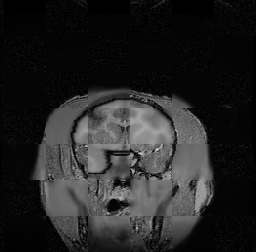

For each of the 10 subjects, we show checkerboard slices in each direction (1) before registration, first row; (2) after rigid->scaleversor->affine registration, second row; and (3) after BSpline registration, third row.

Calvin